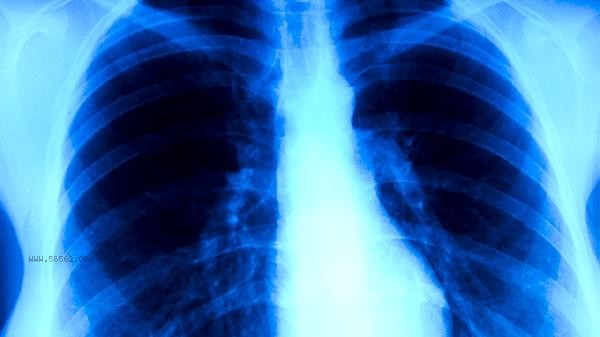

Chinese medicine treatment of lung cancer can be carried out through Chinese medicine conditioning, acupuncture and moxibustion, moxibustion, Qigong, diet and other methods. Lung cancer may be related to long-term smoking, environmental pollution, genetic factors, occupational exposure, chronic lung diseases, and other factors. It usually manifests as symptoms such as cough, chest pain, hemoptysis, difficulty breathing, and weight loss.